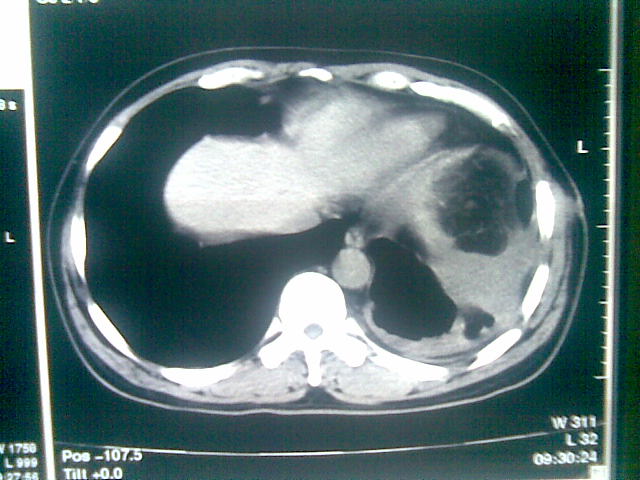

标题: CT23981:男,38岁阑尾炎术后透视胸腔积夜!做CT如下!积液包 [打印本页]

标题: CT23981:男,38岁阑尾炎术后透视胸腔积夜!做CT如下!积液包

可能与阑尾术后关系不太大,1.胸膜增厚粘连见少量气体。包裹脓气胸?左侧网膜囊脓肿?

.胸膜增厚粘连见少量气体。包裹脓气胸

左侧胸膜增厚、粘连+包裹液气胸。